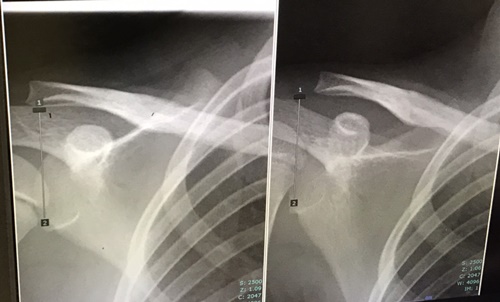

念のため診てもらおうと病院で検査してもらった結果、なんと鎖骨骨折で全治3か月の大怪我であることが判明。

レントゲン写真を見た時、とてもショックでした。

鎖骨が完全に折れていました。この大けがに気付けなかったことが親として本当に情けなかった。

鎖骨をまっすぐにつなげるために鎖骨内に金属棒を入れる手術をすることになり、手術は骨折した日から5日後に行なってもらいました。

金属棒取り外しの手術は、2021年2月初旬でした。

【骨折の状態】

【金属棒取り外し直前の状態】